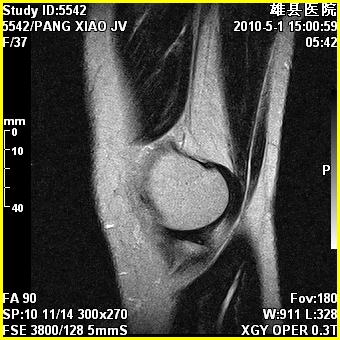

标题: MRI2894:患者右膝关节疼痛两月余,无明显外伤史 [打印本页]

标题: MRI2894:患者右膝关节疼痛两月余,无明显外伤史

右股骨下端前内侧类圆形异常信号,位于干骺端,呈长t1长t2改变,但信号不均,t1图上病灶中心见小片状稍高信号影,t2图上见散在稍低信号影,stir像呈高信号,因病灶较小,缺乏特征性改变,结合患者年龄及部位,考虑嗜酸性肉芽肿可能性大。胫骨关节面下的小囊状异常信号,如果一元论考虑则为嗜酸性肉芽肿,不过发生在这个部位的少见,二元论考虑为邻关节骨囊肿。半月板与前后交叉韧带均未见异常。

右股骨下端前内侧干骺端囊性良性病变,考虑 1内生软骨瘤 2骨囊肿 3肉芽肿。